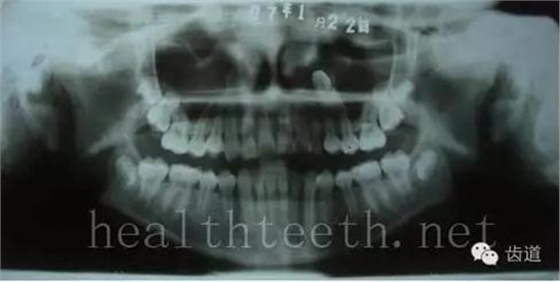

青少年牙周炎,20多歲牙齒破壞到這個程度